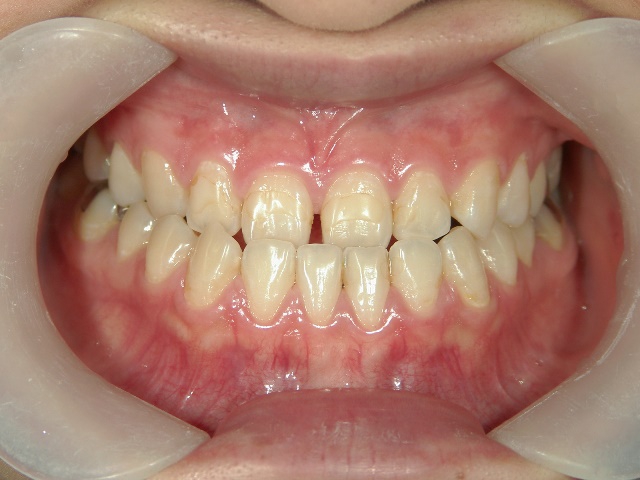

矯正歯科 治療後矯正歯科 全顎ワイヤー矯正 治療後矯正歯科(全顎ワイヤー矯正)治療後

主訴:受け口(反対咬合)を治したい

矯正歯科 治療後

no.31_7964_治療後_右 .JPGno.31_7964_治療後_正面 .JPGno.31_7964_治療後_左.JPG